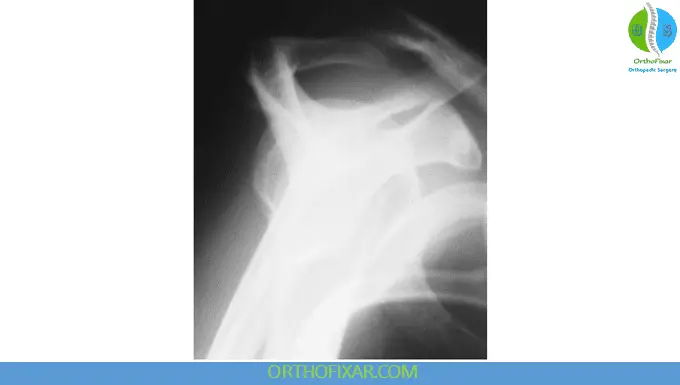

Anteroposterior (AP) View

This projection can be obtained as either a true AP view or a tilt view.

The shoulder AP view allows comprehensive evaluation of several critical anatomical relationships and pathological conditions that include:

1. Glenohumeral Joint Assessment: One of the most important diagnostic signs to recognize is the “empty glenoid” sign, which may indicate posterior shoulder dislocation. In normal anatomy, the radiograph demonstrates overlapping shadows of the humerus and glenoid. When a posterior dislocation occurs, this shadow becomes reduced or completely absent, creating the characteristic empty appearance of the glenoid fossa.

2. Acromioclavicular Joint Evaluation: The AP view provides excellent visualization for assessing acromioclavicular joint width, identifying spurring of the undersurface, evaluating lateral tilt of the acromion, and measuring the critical distance between the humeral head and anterior acromion.

3. Epiphyseal Plate Analysis: Particularly important in pediatric and adolescent patients, the examiner should determine the presence and normalcy of the humeral head epiphyseal plate, which can provide valuable information about growth patterns and potential growth disturbances.

4. Calcific Tendinopathy Detection: The shoulder AP view is excellent for identifying calcifications within the rotator cuff tendons, particularly the supraspinatus and infraspinatus muscles. These calcifications can be indicators of chronic tendinopathy or calcific tendinitis.

5. Acromial Morphology Assessment The configuration of the acromion’s undersurface is an important cause of impingement syndrome of the shoulder. The AP view allows evaluation of acromial shape and the presence of subacromial spurs, which can contribute to rotator cuff pathology.

Hill-Sachs Lesion Identification: When the humerus is positioned in medial rotation during AP imaging, a defect may become visible on the lateral aspect of the humeral head. This defect, known as a Hill-Sachs lesion, represents a compression fracture of the postero-superolateral humeral head resulting from recurrent anterior dislocations. These lesions are classified as either engaged or nonengaged, with engaged lesions articulating with the glenoid during arm abduction and lateral rotation, potentially affecting joint stability.

Reverse Hill-Sachs Lesions: In cases of posterior dislocation, an anteromedial humeral head impression fracture may occur, known as a reverse Hill-Sachs lesion (RHSL), Malgaigne lesion, or McLaughlin lesion. These lesions occur in 30% to 90% of posterior dislocations and can be visualized on plain radiographs, CT scans, or MRI.

Acromiohumeral Interval Measurement: The space between the acromion and humerus, known as the acromiohumeral interval, should measure between 7-14 mm under normal circumstances. A decreased interval may indicate rotator cuff tear, while a coracohumeral distance of less than 11 mm in medial rotation suggests impingement and rotator cuff pathology.

Coracoclavicular Distance: The normal coracoclavicular interspace measures 1.1 to 1.3 cm. This measurement is important when evaluating acromioclavicular joint injuries using stress radiographs with 9 kg weights applied to each hand.